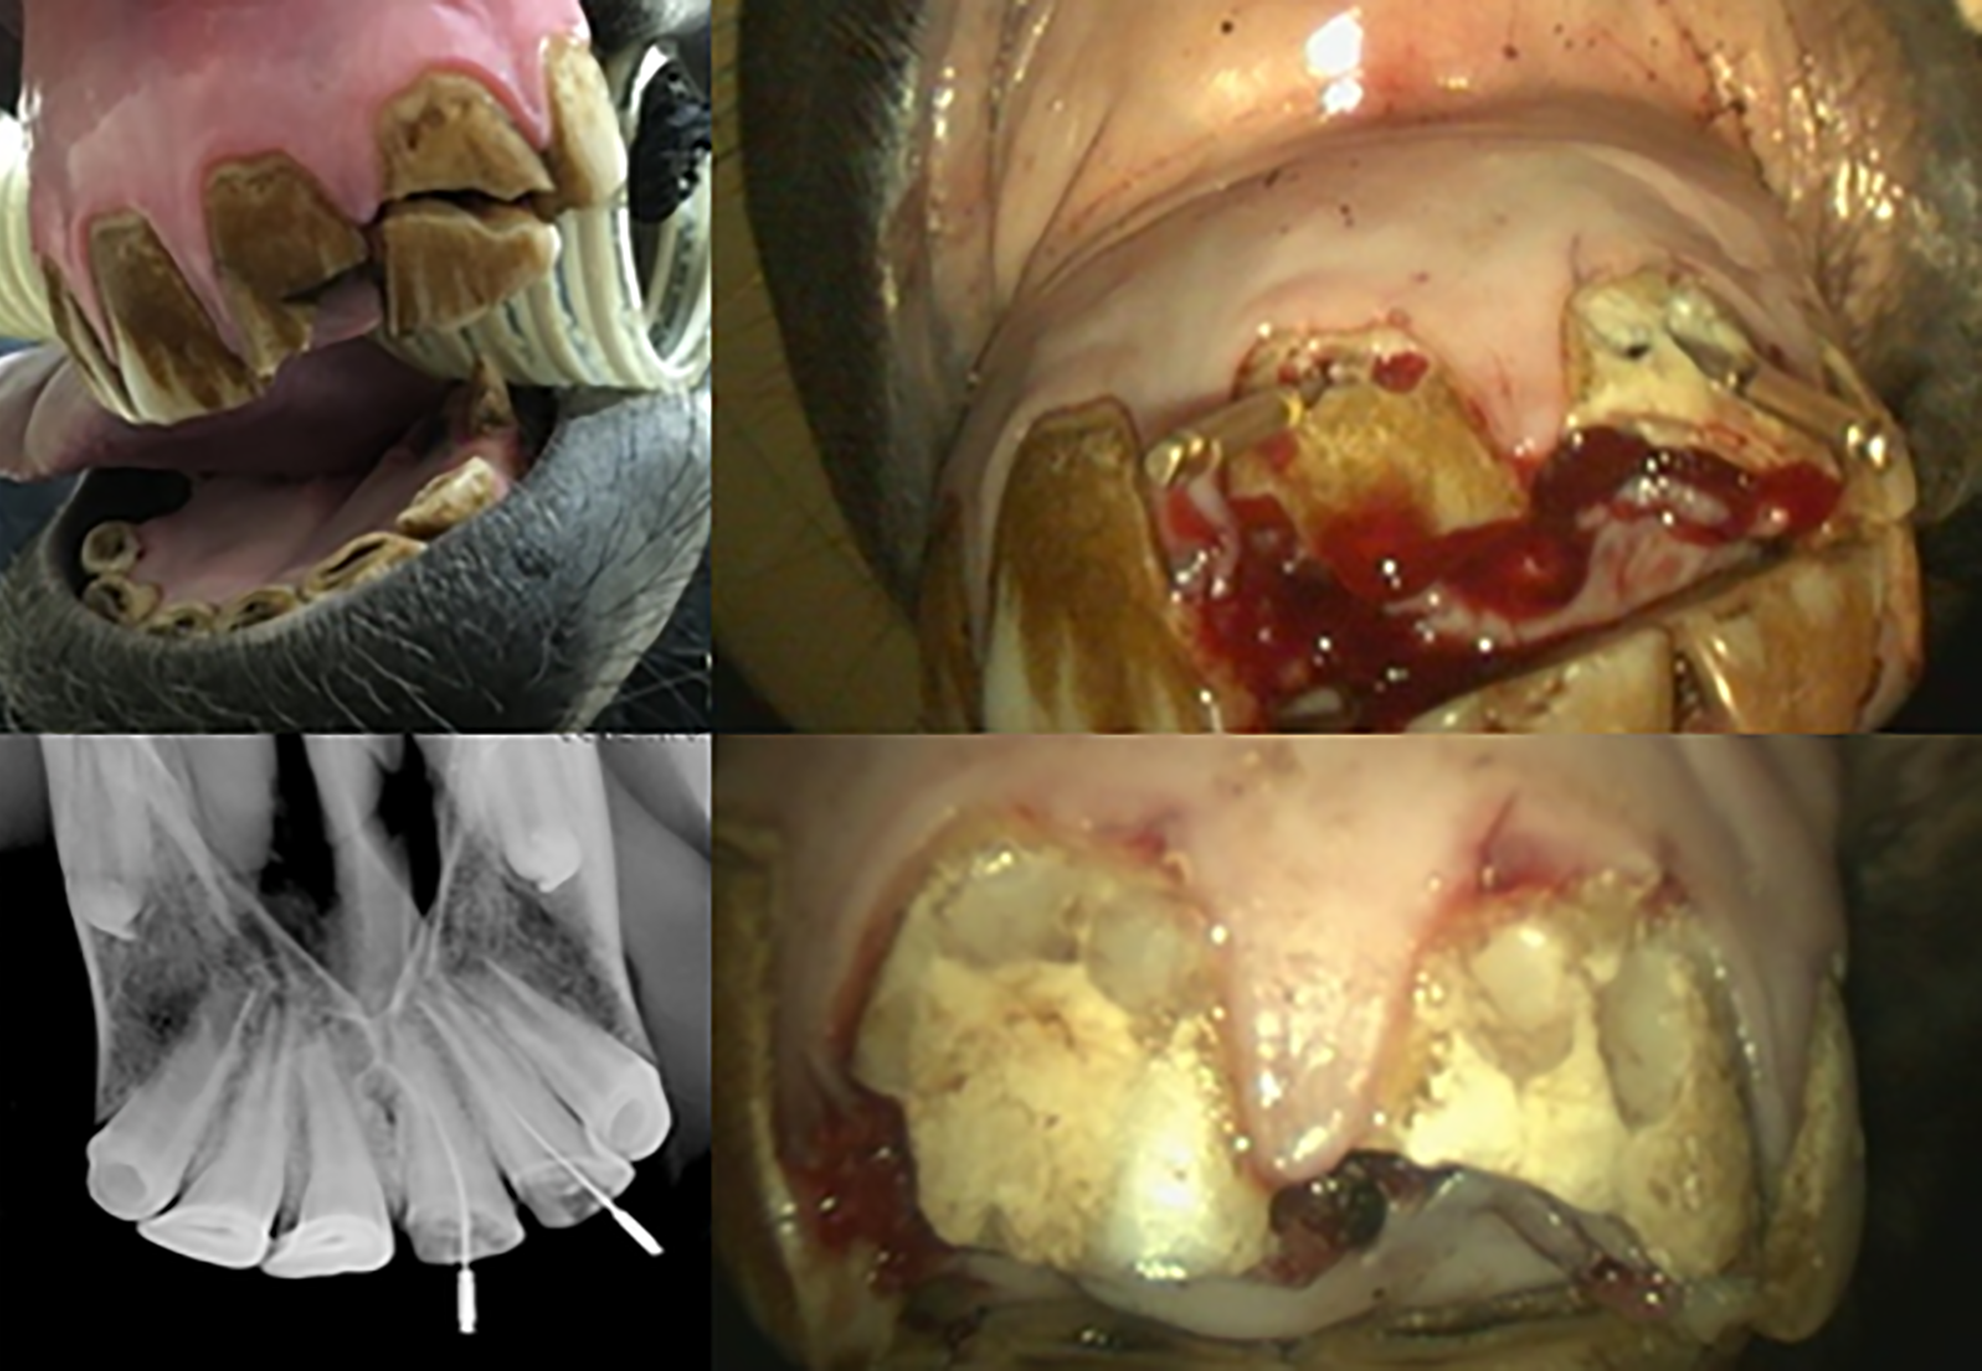

Top left: an acute fracture of upper central and lateral incisor teeth with pulp exposure. Top right: direct endodontic access to the pulp horns at the gum margin. Bottom left: X-ray guidance of debridement depth with dental files. Bottom right: the remaining vital pulp was medicated and the access cavity sealed with a resin composite cement. Credit: John Mark O’Leary MRCVS